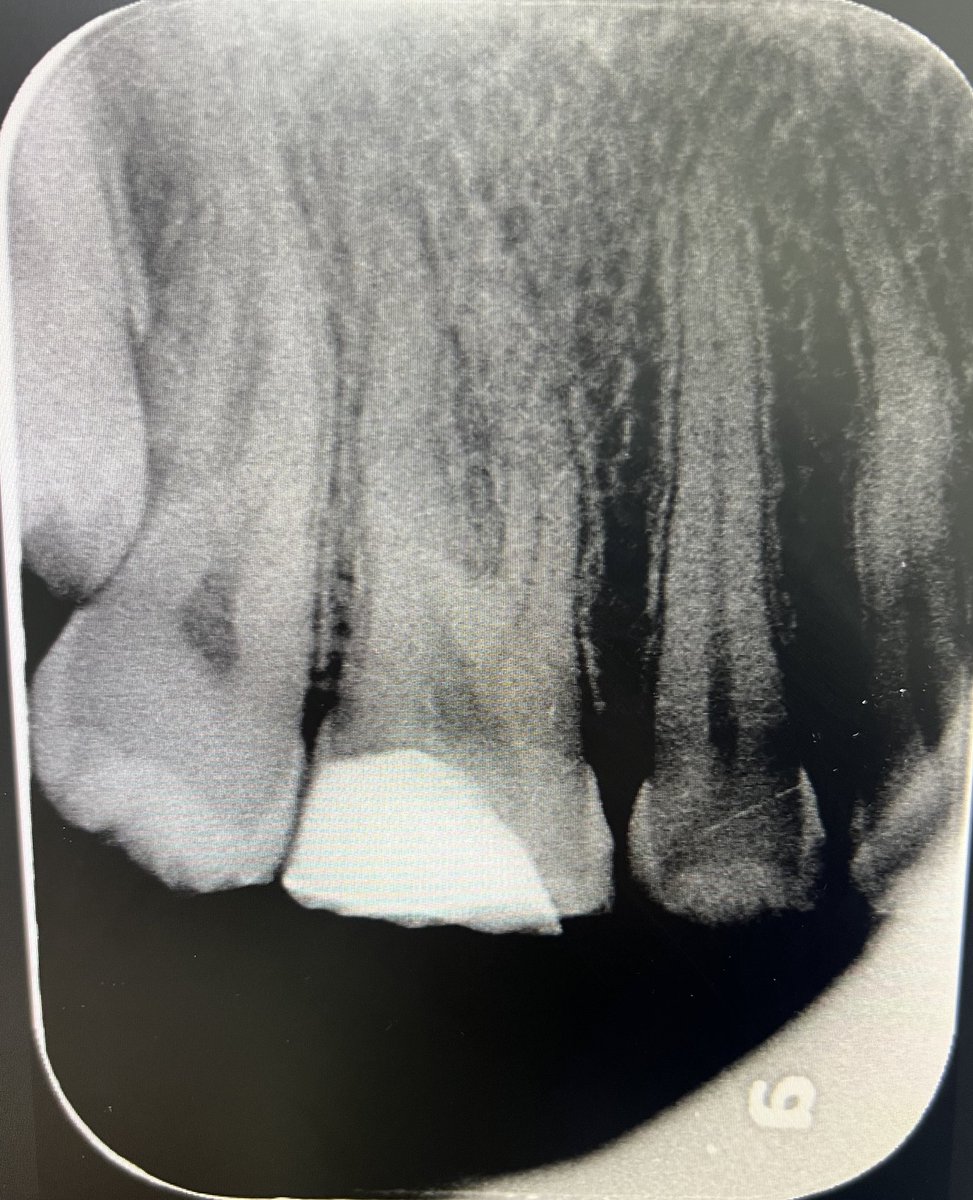

حالة جميلة لصباح اليوم 🙏🏻

Root Canal Treatment #34

Dx:SIP+SAP

Gingival overgrowth and deep caries in the distal wall, Rebuild the distal wall to achieve optimum isolation ✨

Next Step: Crown